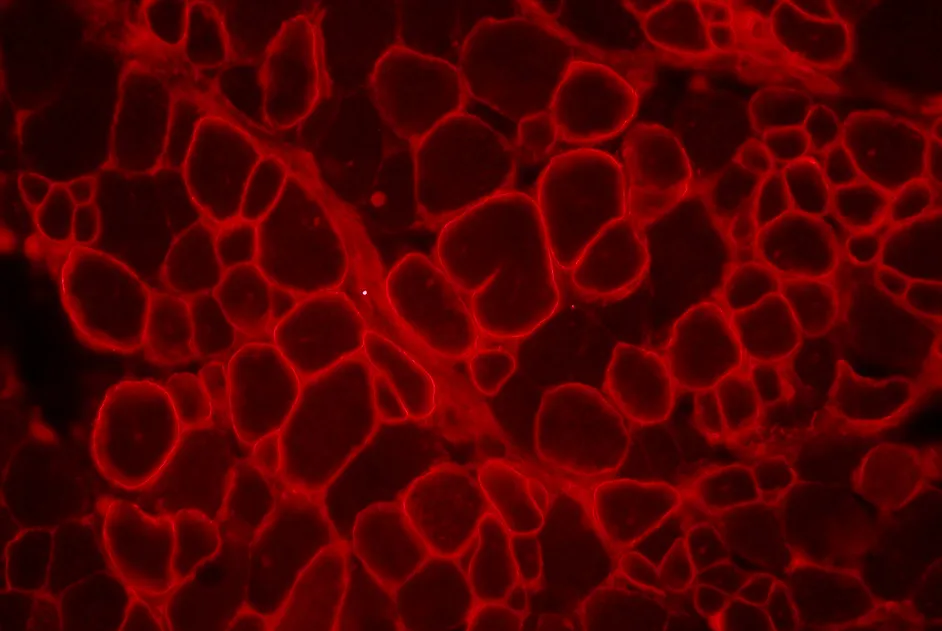

GSK a annoncé une amélioration significative de la marche chez les malades souffrant de myopathie de Duchenne traités durant un an avec le drisapersen qui favorise un saut d’exon ; un essai de phase II auquel l’Institut de Myologie a collaboré.

Amélioration significative de la marche chez les malades atteints de myopathie de Duchenne (DMD) traités 12 mois par drisapersen.